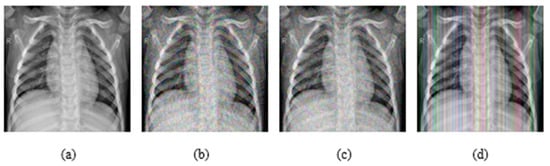

In addition, experiments were performed with FGSM, PGD, and Square Attack for ϵ values equal to 0.01, 0.03, 0.05, 0.07, 0.09, 0.12, and 0.15. In Figure 6, MRI with aforementioned attacks and ϵ = 0.01 are presented. The human eye cannot understand any difference between these images. In Figure 7, attacks with ϵ = 0.07 are depicted. Square Attack causes the biggest distortion compared to FGSM and PGD. However, small changes can be observed also in the other two attacks. In Figure 8, the ϵ value has been increased to 0.15, making the noise perceptible.

Figure 8.

(a) Initial Image, (b) FGSM attack with ϵ = 0.15, (c) PGD attack with ϵ = 0.15, (d) Square Attack with ϵ = 0.15.